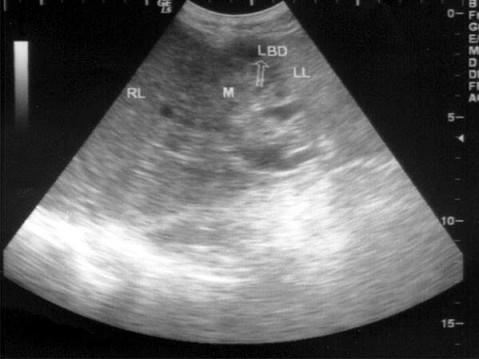

问题 患者男56岁,上腹部疼痛不适1个月余。体检:皮肤、巩膜进行性黄染,上腹部叩击痛(+),B超检查如图所示,根据超声声像图,诊断为?(?)

选项 A.胆管细胞性肝癌 B.肝内胆管结石 C.肝细胞性肝癌 D.肝脓肿 E.肝囊肿

答案 A